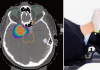

[제주, 제주인의 건강보고서 Ⅷ 건강다이어리] (160)고관절 이형성증

타고난 관절 구조가 원인특히 여성에게 자주 발병퇴행성 관절염으로 이어져조기 진단·맞…

[제주, 제주인의 건강보고서 Ⅷ 건강다이어리] (158)대퇴골두 무혈성 괴사

고관절 통증·절뚝거림 유발음주·스테로이드 주요 원인MRI 검사로 초기 진단 가능단계에 …